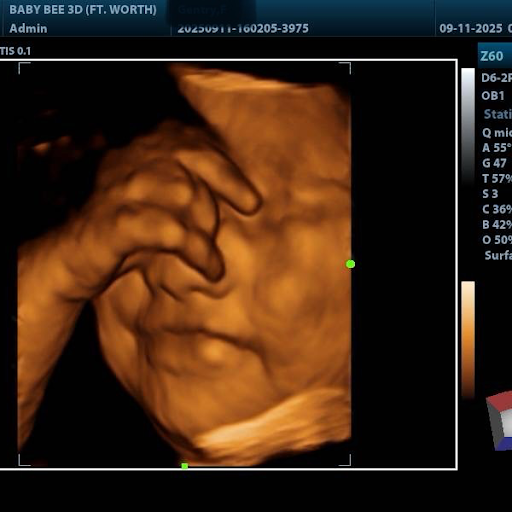

Baby Bee 3D Ultrasound + Photography Studio (Arlington)

By Appointment Only, Online Booking Available. Bring up to 5-7 Guests Expecting Moms, Experience the Joy of Connecting with Your Baby: Ultrasound 2D, 3D, and 4D Ultrasounds Sonograms Hear and See Your Baby’s Heartbeat Early Pregnancy Confirmation Gender Determination from 14 Weeks 6-Week Gender Blood Test (Next Business Day Results) Create unforgettable memories and share these precious moments with your loved ones. In Studio Maternity Photography availability.